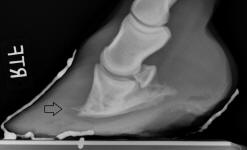

A New 464 Page Textbook, in Full-Color with 630 Pictures and Drawings, by Pete Ramey

A Few Pictures from the book:

Photos referenced in text from Bidwell/Bowker, Bowker, Clayton, Cowles, Hampson, Kellon, Ramey, Ridgway, Sullivan, Taylor, Watts.